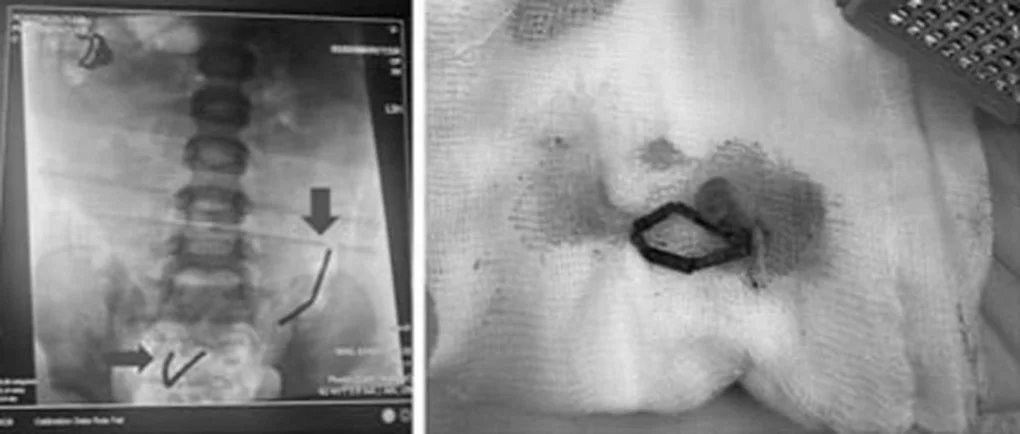

Hai chuỗi nam châm dài được ghi nhận trong ruột non trẻ (Ảnh: BV)

Tại đây, trẻ biểu hiện đau bụng, nôn ói, quấy khóc, chụp X-quang bụng phát hiện dị vật nằm theo chuỗi ở ruột non. Kết quả siêu âm ghi nhận tình trạng viêm ruột, viêm phúc mạc. Trẻ được chuyển mổ nội soi ngay sau đó.

Trong quá trình phẫu thuật, các bác sĩ phát hiện ruột non bệnh nhi bị thủng 8 lỗ, mỗi lỗ có đường kính khoảng 2-3mm. Ê-kíp đã vá lại toàn bộ lỗ thủng, lấy ra 2 chuỗi nam châm, tổng cộng 20 viên. Các viên nam châm đã gỉ sét, gây tổn thương ruột nghiêm trọng.